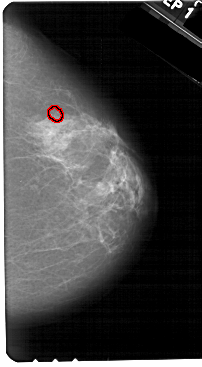

A_1328_1.LEFT_CC

LEFT_CC LINES 5491 PIXELS_PER_LINE 3136 BITS_PER_PIXEL 12 RESOLUTION 43.5 NON_OVERLAY

FILE: A_1328_1.RIGHT_CC.OVERLAY

TOTAL_ABNORMALITIES 1

ABNORMALITY 1

LESION_TYPE CALCIFICATION TYPE PLEOMORPHIC DISTRIBUTION CLUSTERED

ASSESSMENT 4

SUBTLETY 5

PATHOLOGY BENIGN

TOTAL_OUTLINES 1